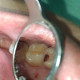

Alo dokter π Saya ingin mendiskusikan kasus saya.. Pasien dtg dengan keluhan gigi sering terselip makanan.

Pemeriksaan klinis gigi 25, karies proksimal mencapai sub gingiva. Yg terlihat di foto adalah gigi 25 setelah saya bersihkan karies seadanya, karena gingiva antara 25 dan 26 terus berdarah.

Ternyata setelah gigi 25 dibersihkan, gigi 26 karies juga di proximal. Proses pembuangan karies 25 sulit sekali, karena gingiva berulang kali berdarah. Penekanan dengan cotton pellet povidone iodine tidak memberi efek apa2.